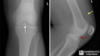

3

lipohemarthrosis. results from an intra-articular fracture with escape of fat and blood from the bone marrow into the joint, and is most frequently seen in the knee, associated with a tibial plateau fracture or distal femoral fracture; rarely a patellar fracture XR Subtle tri-layer appearance due to fat on serum on red cells.